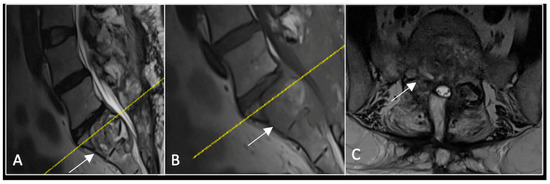

2.4. Case 4: Lumbar Chordoma

This 56-year-old lady was diagnosed with a biopsy-confirmed L2 chordoma (Figure 11). She underwent posterior decompressive separation surgery and instrumental stabilisation T12-L4 using carbon-based implants (Figure 12). Surveillance imaging at 6 months and 12 months post-separation did not show any progression of residual tumour disease (Figure 13 and Figure 14).

Figure 11.

RI demonstrating a lobulated destructive lesion (arrow) with significant epidural extension and compression at L2. The yellow line on the sagittal images denotes the level of the axial image. (A) T2W sagittal; (B) T1W sagittal; (C) T2W axial.